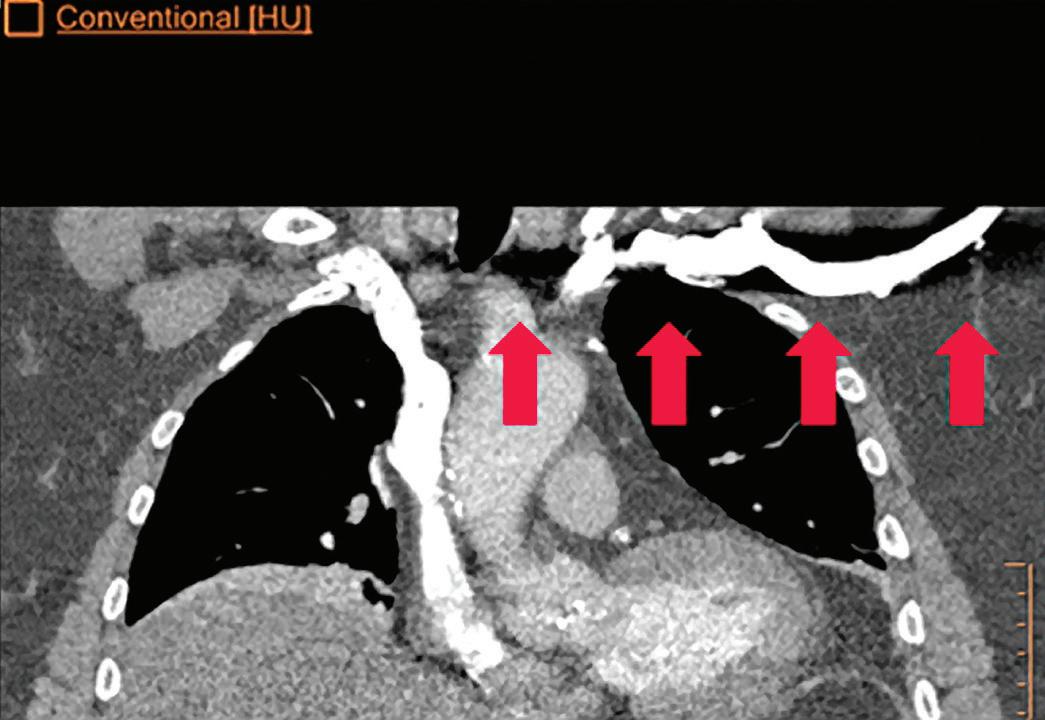

CT breath-hold results in a poor enhancement of the pulmonary arteries on the displays from left to right: monoenergetic 70 keV, monoenergetic 55 keV, monoenergetic 40 keV, and Z effective map showing a perfusion deficit of the lung parenchyma (white arrow). When decreasing the energy, the iodine attenuation is progressively boosted and reveals the presence of a thrombus (colored arrows) in a sub-segmental pulmonary artery corresponding to the territory of the perfusion deficit. (c) Monoenergetic 200 keV reduces beam hardening from dense contrast medium compared to conventional CT images.

Once the pair (αp, αc) is calculated for every voxel, and since fp(E) and fc(E) are known functions of energy, one may synthesize monochromatic images at different energies. These images can be used for routine diagnosis similar to conventional images. With a single scan at 120 kVp (or 140 kVp for obese patients), a dual-layer spectral CT acquisition allows the reconstruction of virtual monochromatic images from 40 keV up to 200 keV, in increments of 1 keV. The minimum of 40 keV was chosen in order to stay above the k-edge of the most common materials including iodine (iodine k-edge = 33 keV). If the scan is performed at 120 kVp, the conventional CT images of a typical-size patient will display an attenuation corresponding to the average of the X-ray spectrum (˜70 keV in a body scan) but with beam hardening artifacts from dense structures (like bones) which are due to the polychromatic nature of the X-ray beam. Since the photoelectric effect is dominant at lower keV, and is relatively high for high Z materials, low keV imaging (below 70 keV for body) can be used to enhance the absorption of high Z material such as iodine (Z=53), compared to the conventional CT images.15,16 This can be of particular interest to enhance the iodine uptake for patients with renal dysfunction, where the total injected volume of iodinated contrast medium is very limited. This attenuation boost can also be very useful in the case of a missed injection (Figure 2a and b). Compton scattering on the other hand is dominant at higher keVs and does not exhibit a strong relationship with Z. High keV imaging will then be of particular interest to minimize the absorption of high Z materials and minimize all types of associated artifacts (metal beam hardening from metal implants, beam hardening from dense contrast medium, blooming of stents or calcium, etc.) (Figure 2c).17,18,19